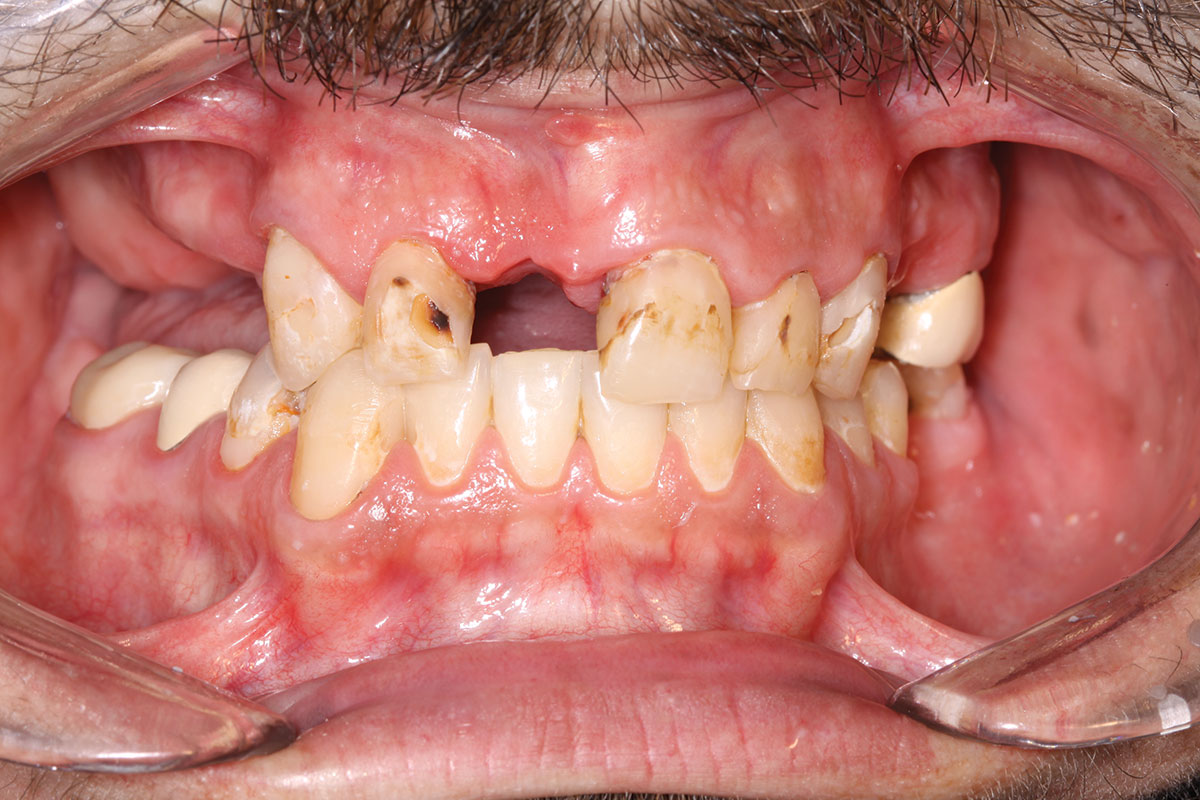

Fig 27. Preoperative view of mandible.

Figure 27

Case 3

A 67-year-old female patient presented with a highly compromised maxillary and mandibular dentition, including teeth Nos. 2 through 15, 17, 21 through 24, and 27 through 30. Soft tissues were of normal contour, and bone profiles were generally sustained and favorable. The patient was excited about the prospect of transforming both her maxillary and mandibular compromised esthetics and function in one visit. (Case 3 is depicted in Figure 23 through Figure 42.)